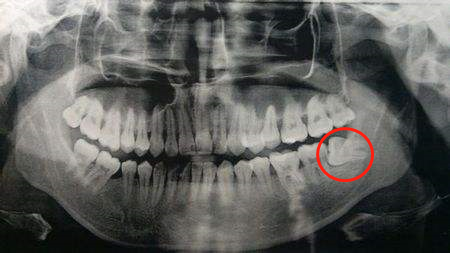

有些拔除智齒較晚的小伙伴(25周歲以上),由于智齒長(zhǎng)期椅靠在旁邊的第二磨牙處,使其嚴(yán)重受損。

導(dǎo)致第二磨牙的牙槽也嚴(yán)重吸收。

這種情況下是可以考慮進(jìn)行位點(diǎn)保存手術(shù)的。如圖——